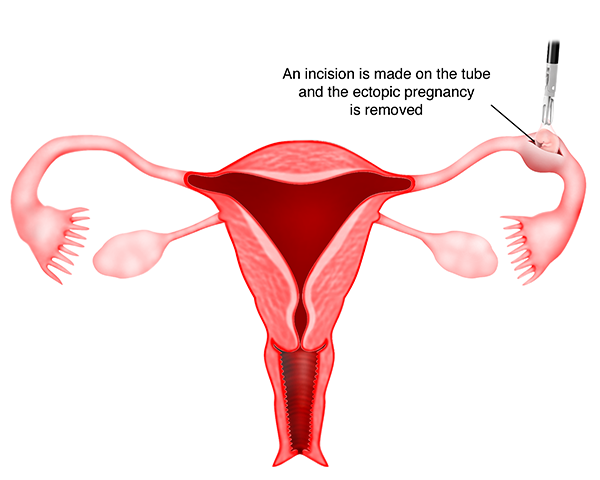

2) Salpingostomi Laparoskopi

Dalam teknik ini, sayatan dibuat di perbatasan antimesenterika (g) ( bagian dari tuba yang berlawanan dengan mesosalping (g) dari tuba falopi ), dan jaringan ektopik diekstraksi dari tuba. Sayatan pada tuba dapat dijahit atau mungkin tidak dapat dijahit. Apabila sayatan dijahit, operasi ini disebut dengan salpingostomi laparoskopi. Teknik salpingostomi laparoskopi biasanya dilakukan pada kehamilan tuba awal dan tidak pecah.

Keuntungan melakukan teknik ini adalah tuba masi utuh sehingga pasien dapat hamil dengan bantuan tuba ini di yang akan datang.

Kerugiannya adalah karena tuba mengalami bekas luka yang diakibatkan dari operasi, kehamilan ektopik lain dapat terjadi di tempat yang sama, dan juga resiko kecil bahwa setelah operasi beberapa kehamilan ektopik mungkin masih ada dan bisa berkembang di dalam tuba.

Dengan demikian, apabila teknik ini dilakukan, penting untuk melakukan pengulangan test darah ( serum beta HCG ) agar dapat memastikan bahwa tingkatnya telah menurun, sehingga mengindikasikan tidak adanya pertumbuhan yang lebih jauh dari kehamilan ektopik. Histerosalpingografi akan diperlukan setelah 3 bulan untuk memastikan apakah tuba masih paten. Teknik ini biasanya direkomendasikan apabila pasien hanya memiliki 1 tuba paten karena pengangkatan tuba akan memerlukan IVF bagi pasien untuk hamil.